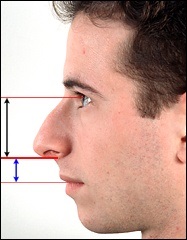

Mielőtt nagyobb acanthion. Ez az, amit úgy néz ki, a művelet során. Az ábrán a jobb ez sárga színű. Acanthion columella található, közvetlenül alatta, ahol a felső ajak határos az alapja az orrát.

Része a gerinc, amelyeket el kell távolítani jelzi a kék vonalon. Removal végezzük vésővel.

Ebben a beteg, ott van a hatás a „kötés” a felső ajak. Photo fenti elégedett üzemeltetés előtt. Fekete jelzi a helyzetét az első kiálló orr-gerinc. A kék vonalat húzott a jobb megítélése a profilt. Ha a hatása „árukapcsolás” a felső ajak vonal irányította a profilját Vered és legfeljebb az alap az orr.